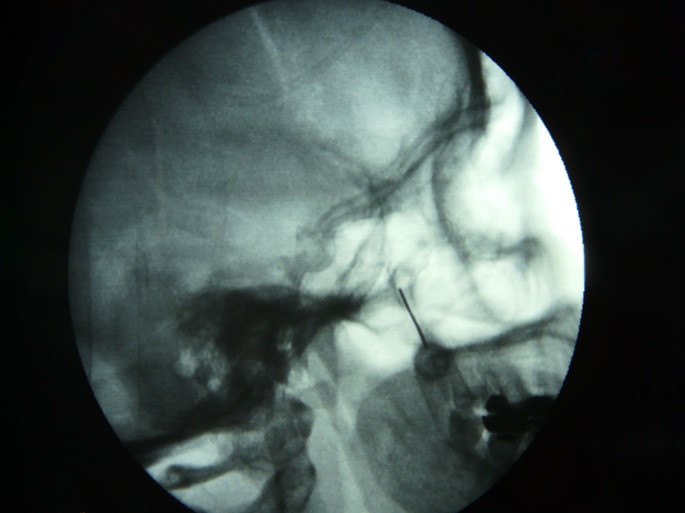

Fig.4. Adecuada colocación de la aguja en su trayecto infra cigomático y penetración en la fosa Ptrigopalatina

Fig.5. En esta proyección lateral se observa la aguja posicionada en la fosa ptrigopalatina como referencia guía y la Crio sonda colocada en la cavidad para realizar la crio lisis.

Fig.6. El paciente se coloca en posición decúbito supino, y en proyección lateral el fluoroscopio emite su haz de rayos a la base del cráneo, se alinean las ramas horizontales y verticales mandibulares para que estén en un mismo plano, esto es fundamental para superponer las dos fosas Pterigomaxilares y puedan visualizarse como una sola, y no se fije una falsa diana, visualizando la fosa del lado contrario y tomarla de forma equivocada.

Fig.7. Introduccción de la aguja hasta la fosa Ptrigopalatina bajo control fluoroscopico en tiempo real con abordaje infra cigomático.